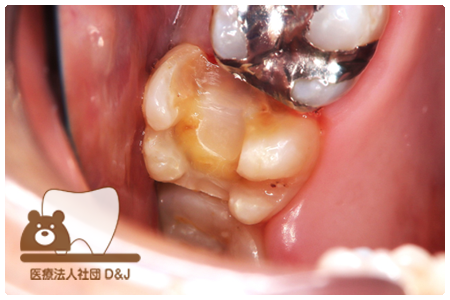

症例8フルジルコニアクラウン

治療前

治療中

治療後

29歳 女性

- 治療内容

- 銀歯からフルジルコニアクラウンへの修復

- 治療期間

- 根の治療含め3か月

- 費用

- 自費

フルジルコニアクラウン:77,000円(税込)

- その他の治療の費用は含まれておりません。

- リスク・副作用

- 強い衝撃が加わると欠けたり割れたりする可能性があります。また、噛み合わせの状態によっては脱離や周囲の歯への影響が出ることもあります。